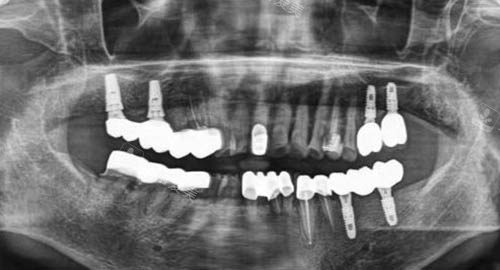

之后,可靠的医生会对患者进行详细的口腔检查,包括口腔内部情况的观察、X光等必要的检查项目,以较准诊断病情。

多颗牙齿种植ct